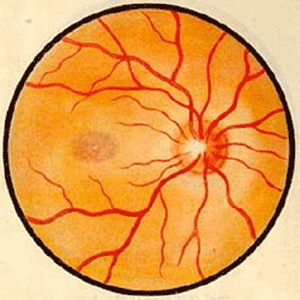

视神经病变

宜昌6686 - 看球聊球追世界杯就来6686体育有限公司官方网站中医眼科主任秦大军接连为视神经病变患者医治